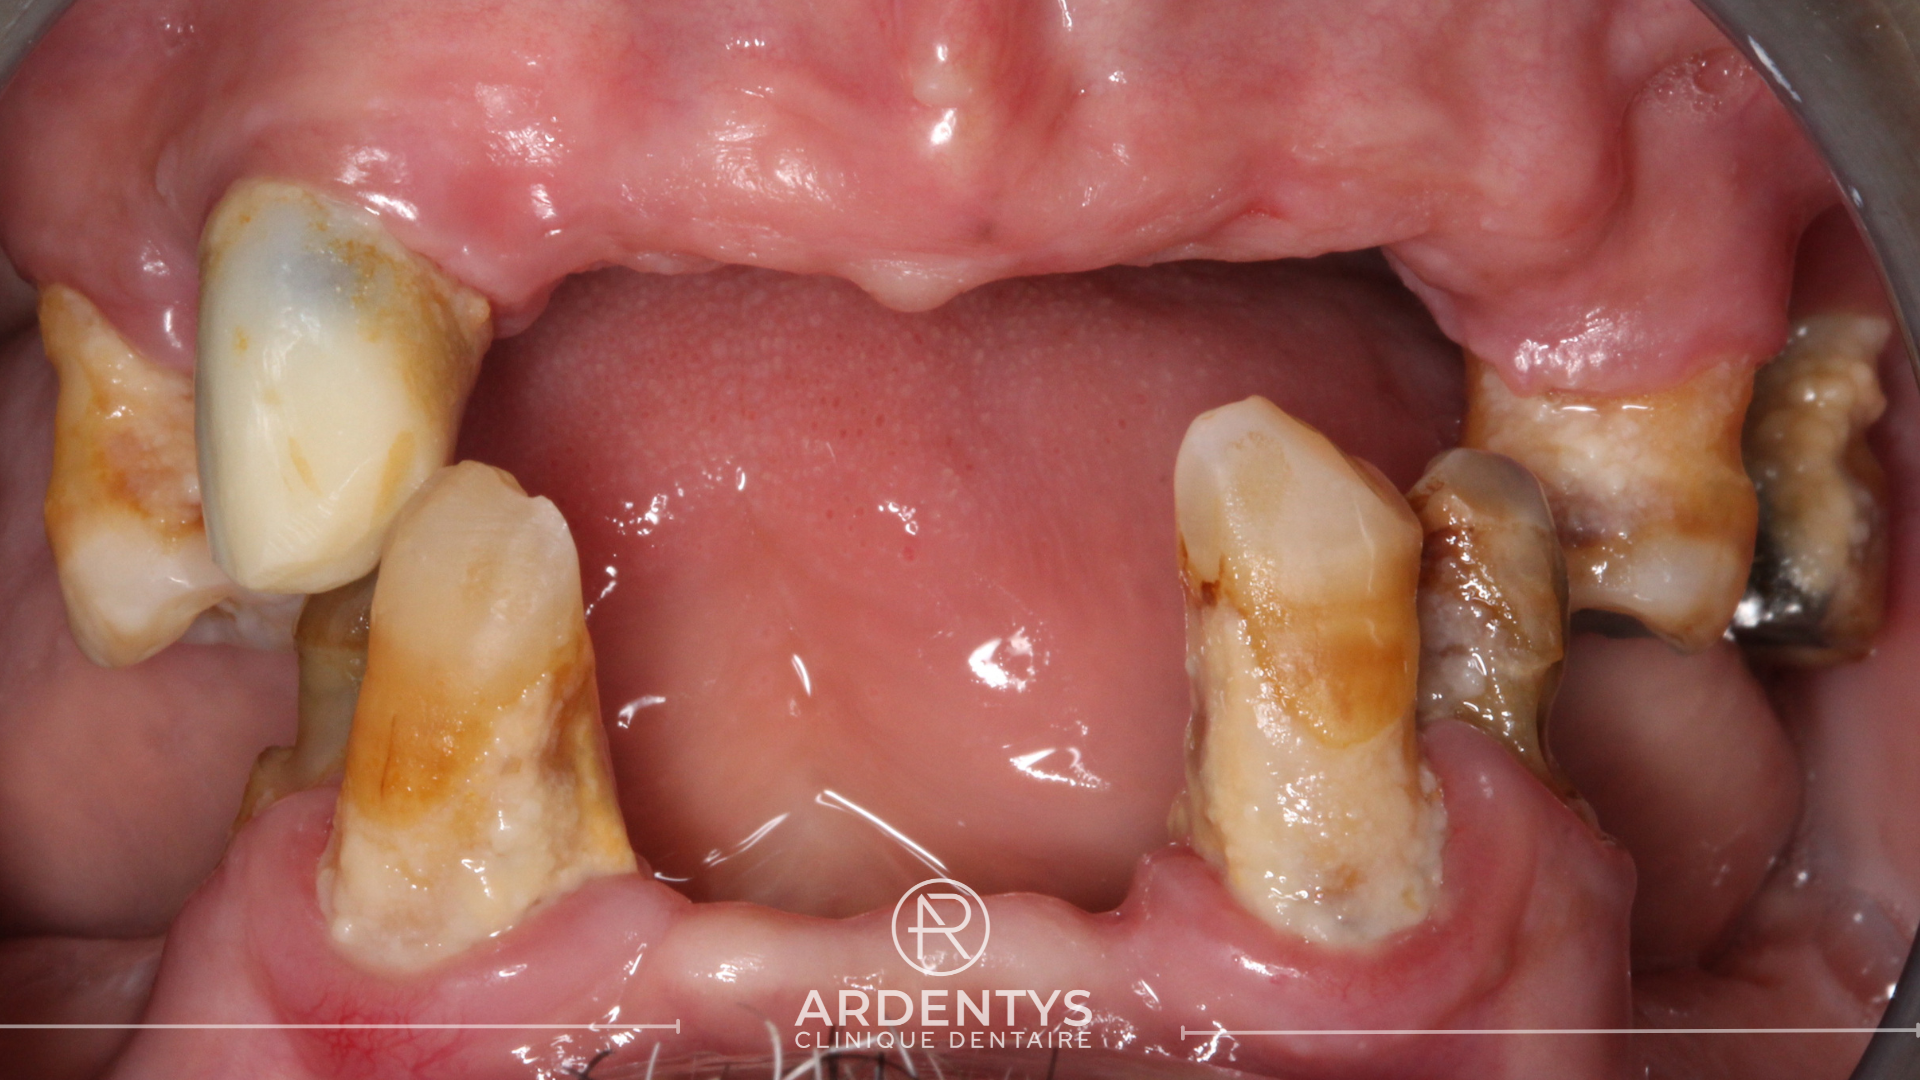

Réhabilitation complète bi maxillaire